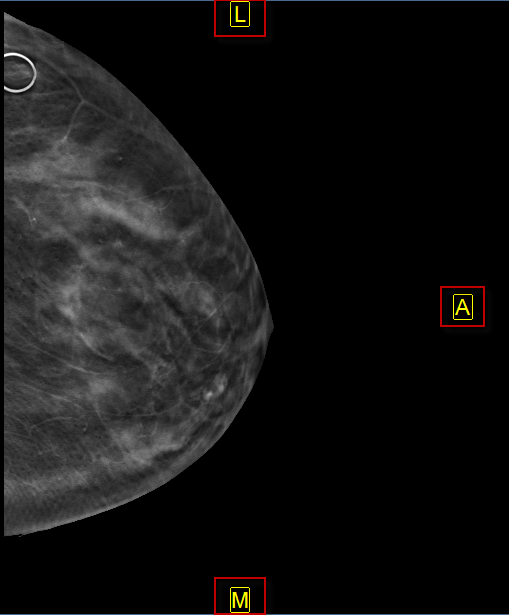

Az alábbi képek egy orrmelléküregi CT-t és egy mammográfiát ábrázolnak, amelyen automatikus orientáció van alkalmazva.

Az automatikus orientáció funkció felülírja a modalitás által meghatározott alapértelmezett betegorientációt, és a felhasználó által meghatározott orientációt alkalmaz. Ha egy képen automatikus orientációt alkalmaznak, a beteg orientációs mutatói kényszerítetten a képen, sárga színnel jelennek meg.

- Mammográfiás képek a kép háti széle pozíciójának meghatározására.